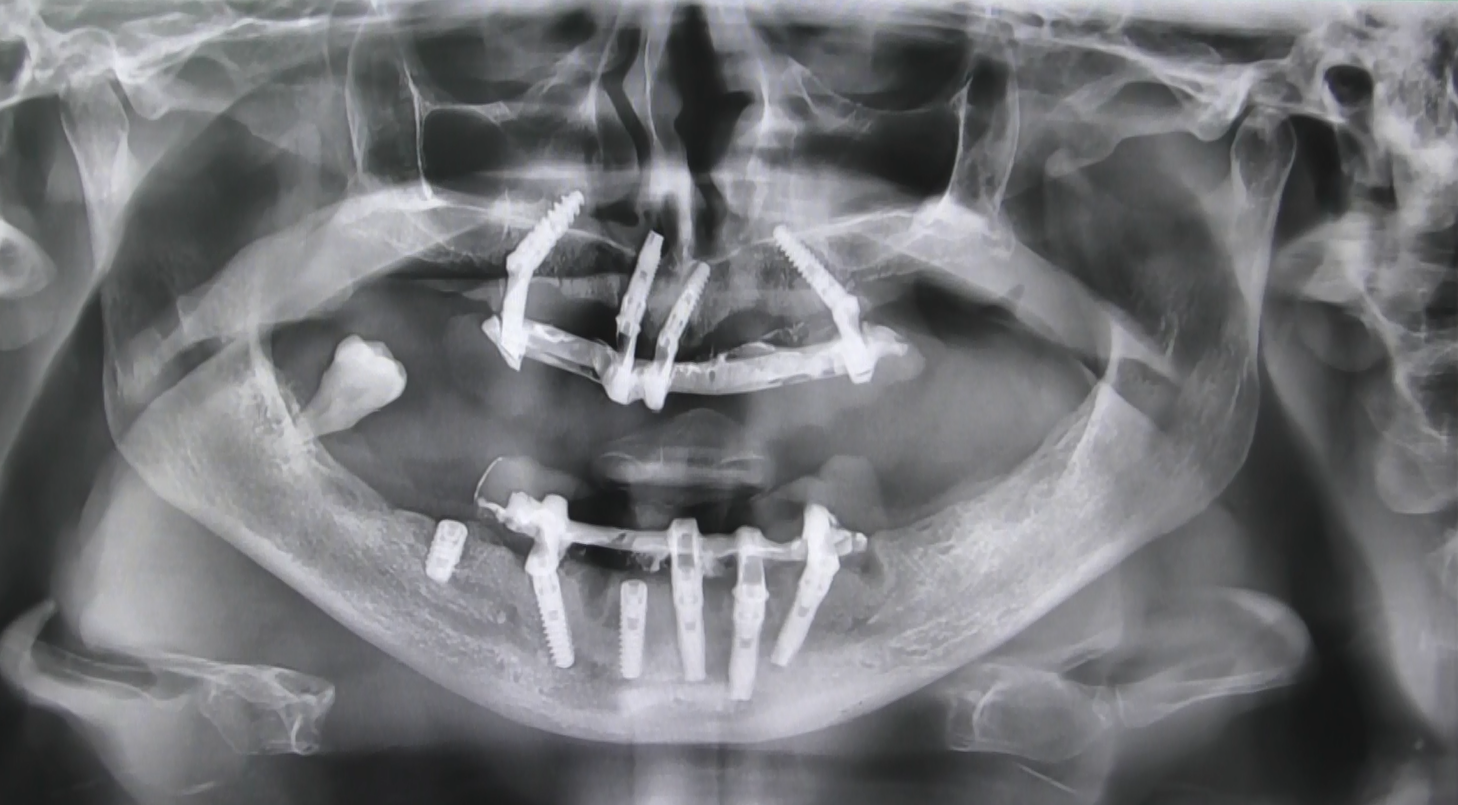

Benvenuti nel nostro centro specialistico in soluzioni atrofiche estetiche a Padova, dove la creazione di un sorriso senza falsa gengiva è una realtà tangibile. Presso la nostra clinica, integriamo la pianificazione dell’implantologia sin dalla prima visita, offrendo una collaborazione sinergica tra l’implantologo e il protesista con oltre 35 anni di esperienza condivisa.

Approccio Personalizzato Fin dalla Prima Visita:

Il nostro team valuta attentamente le condizioni del paziente, registrando le zone con riassorbimenti anomali, atrofie e quelle dell’osso non longilineo. In un’interfaccia diretta tra implantologo e protesista, affrontiamo ogni aspetto negativo, creando un piano personalizzato per il ripristino della masticazione.

Interventi Preventivi per l’Eccellenza Estetica:

Prima dell’intervento implantare, affrontiamo le atrofie e le zone problematiche attraverso interventi preventivi. Il nostro obiettivo è ottenere non solo una funzione masticatoria ottimale ma anche una soluzione estetica preventivata con il paziente. Garantiamo circolari fissi in ceramica senza falsa gengiva, con elementi dentali che emergono naturalmente senza aggiunte antiestetiche.

Collaborazione Implantologo-Protesista:

La stretta collaborazione tra implantologo e protesista è essenziale per garantire un risultato estetico garantito. Ogni passo del processo è sincronizzato per creare un sorriso che rispecchi le aspettative estetiche e funzionali del paziente.